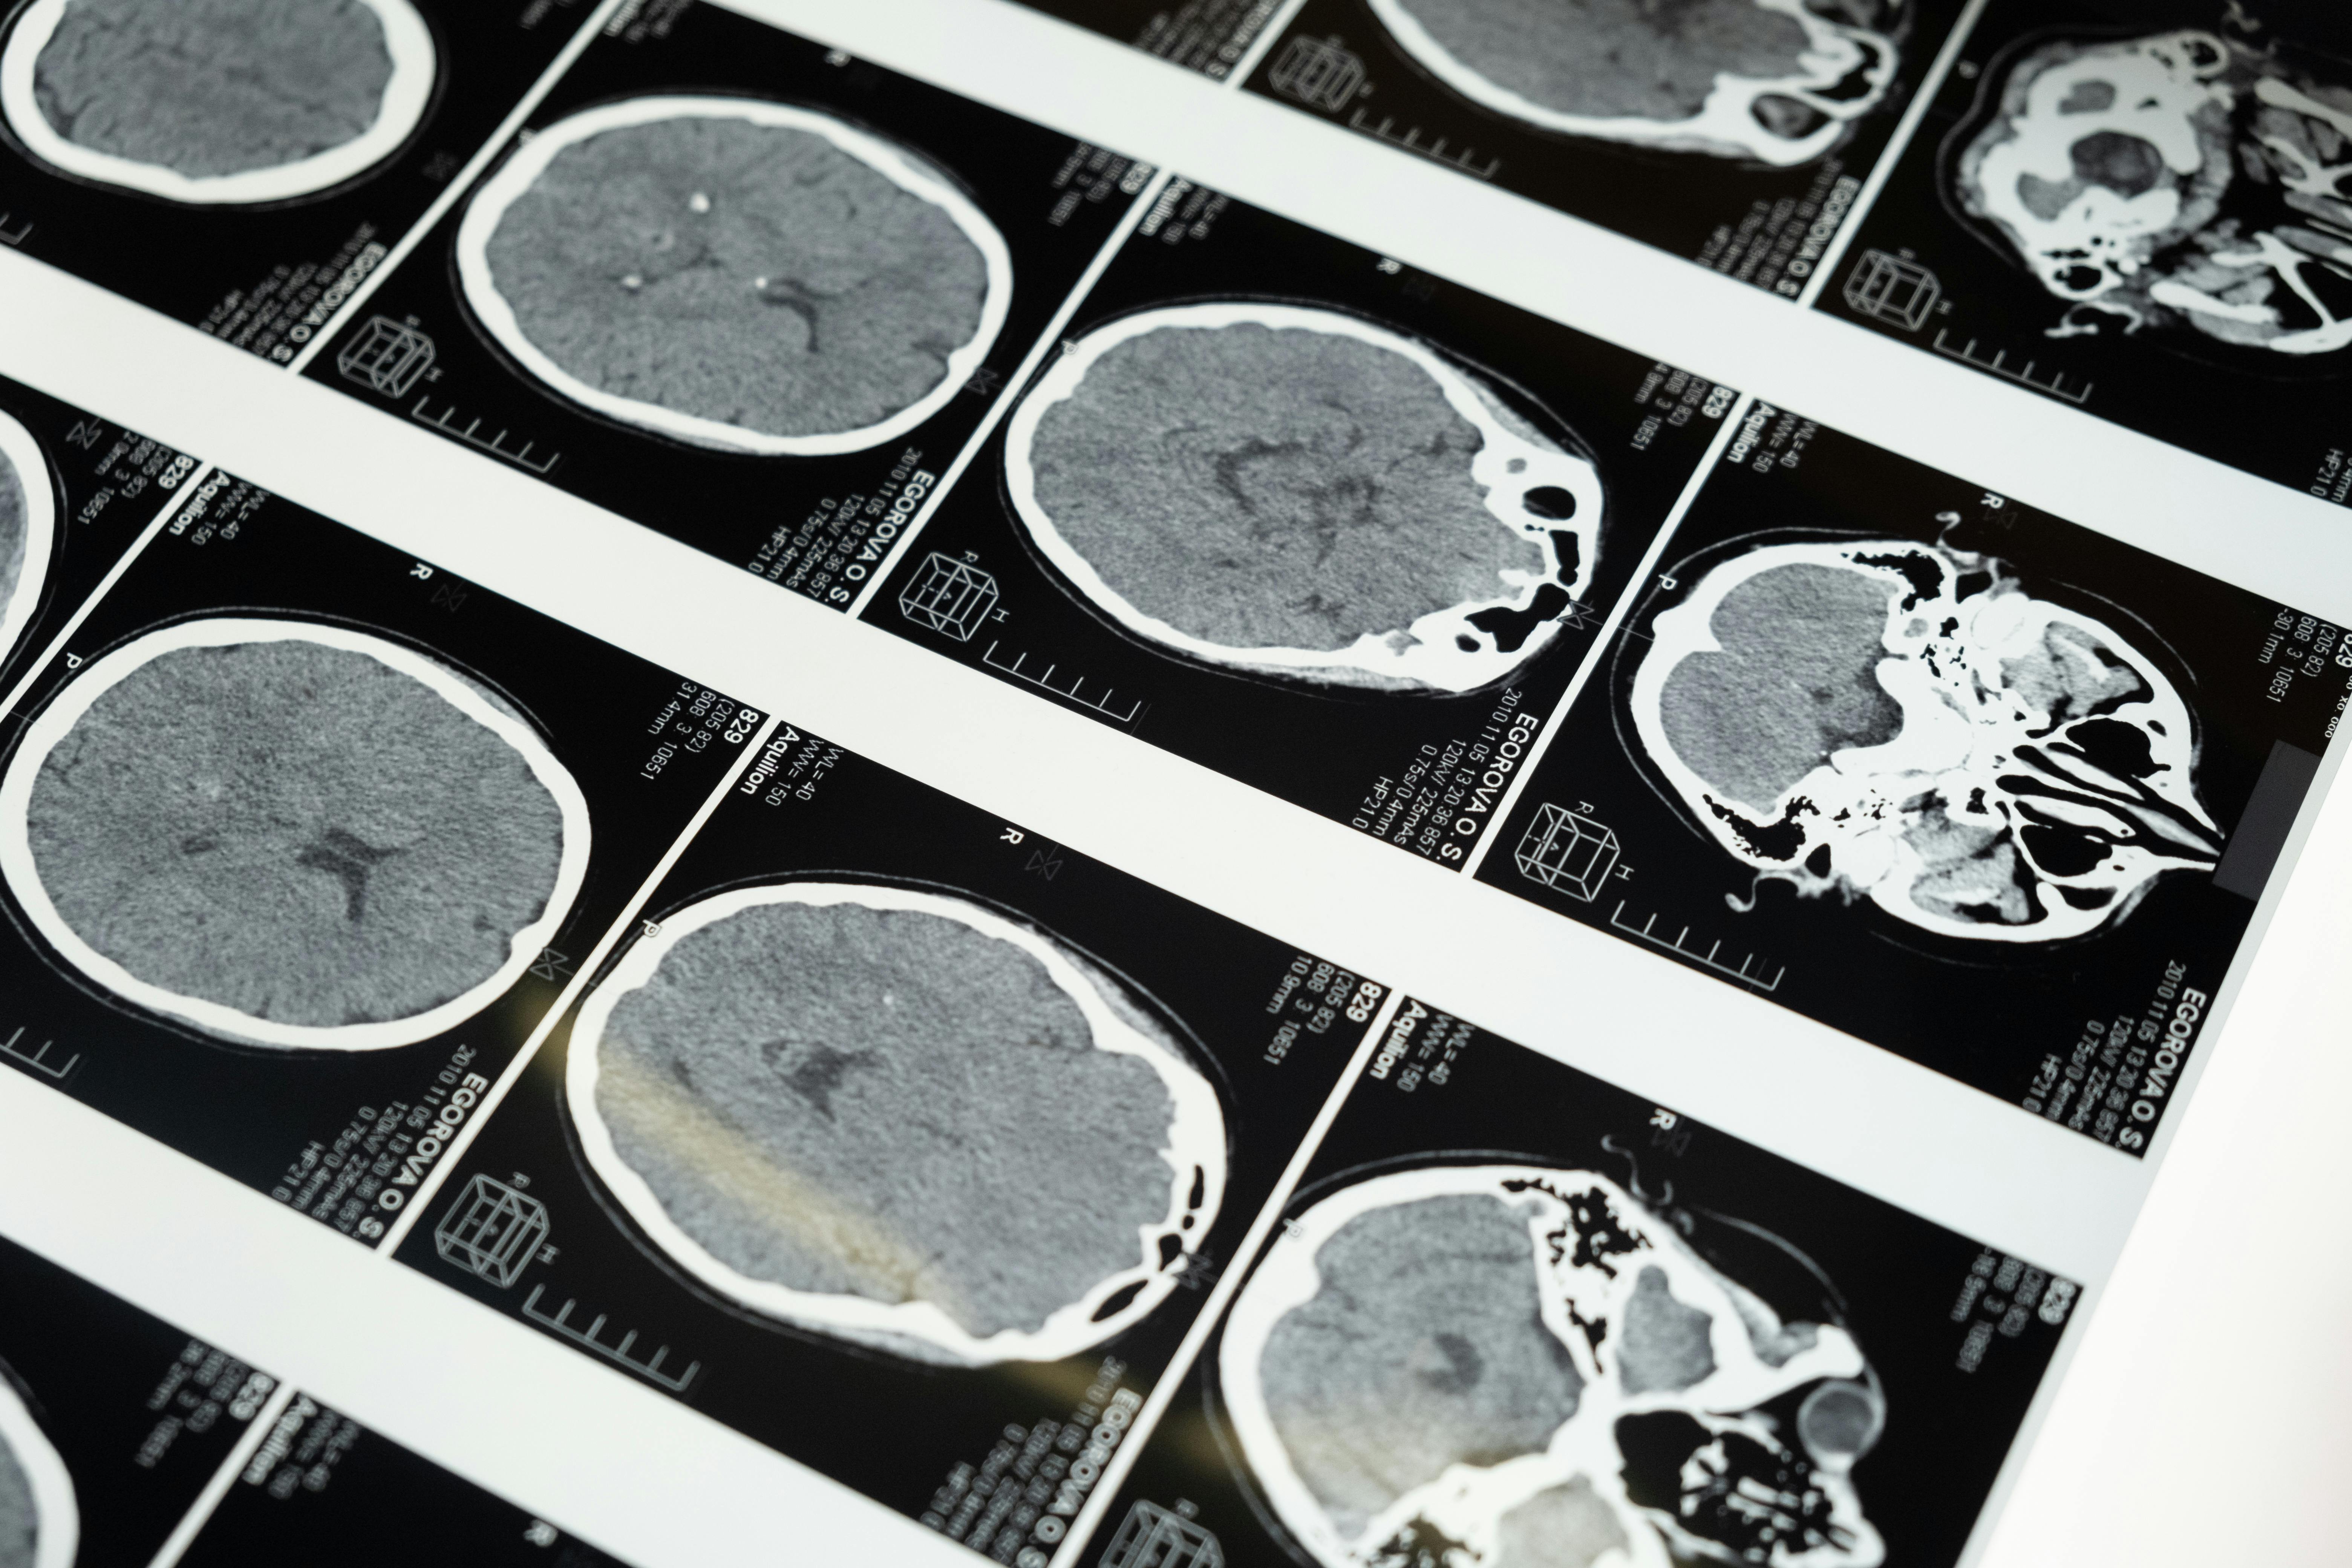

Understanding Concussion Recovery: What Vestibular Rehab Can Do for You

Dizziness, balance problems, and difficulty reading after a concussion? Learn how vestibular rehabilitation can help you recover.